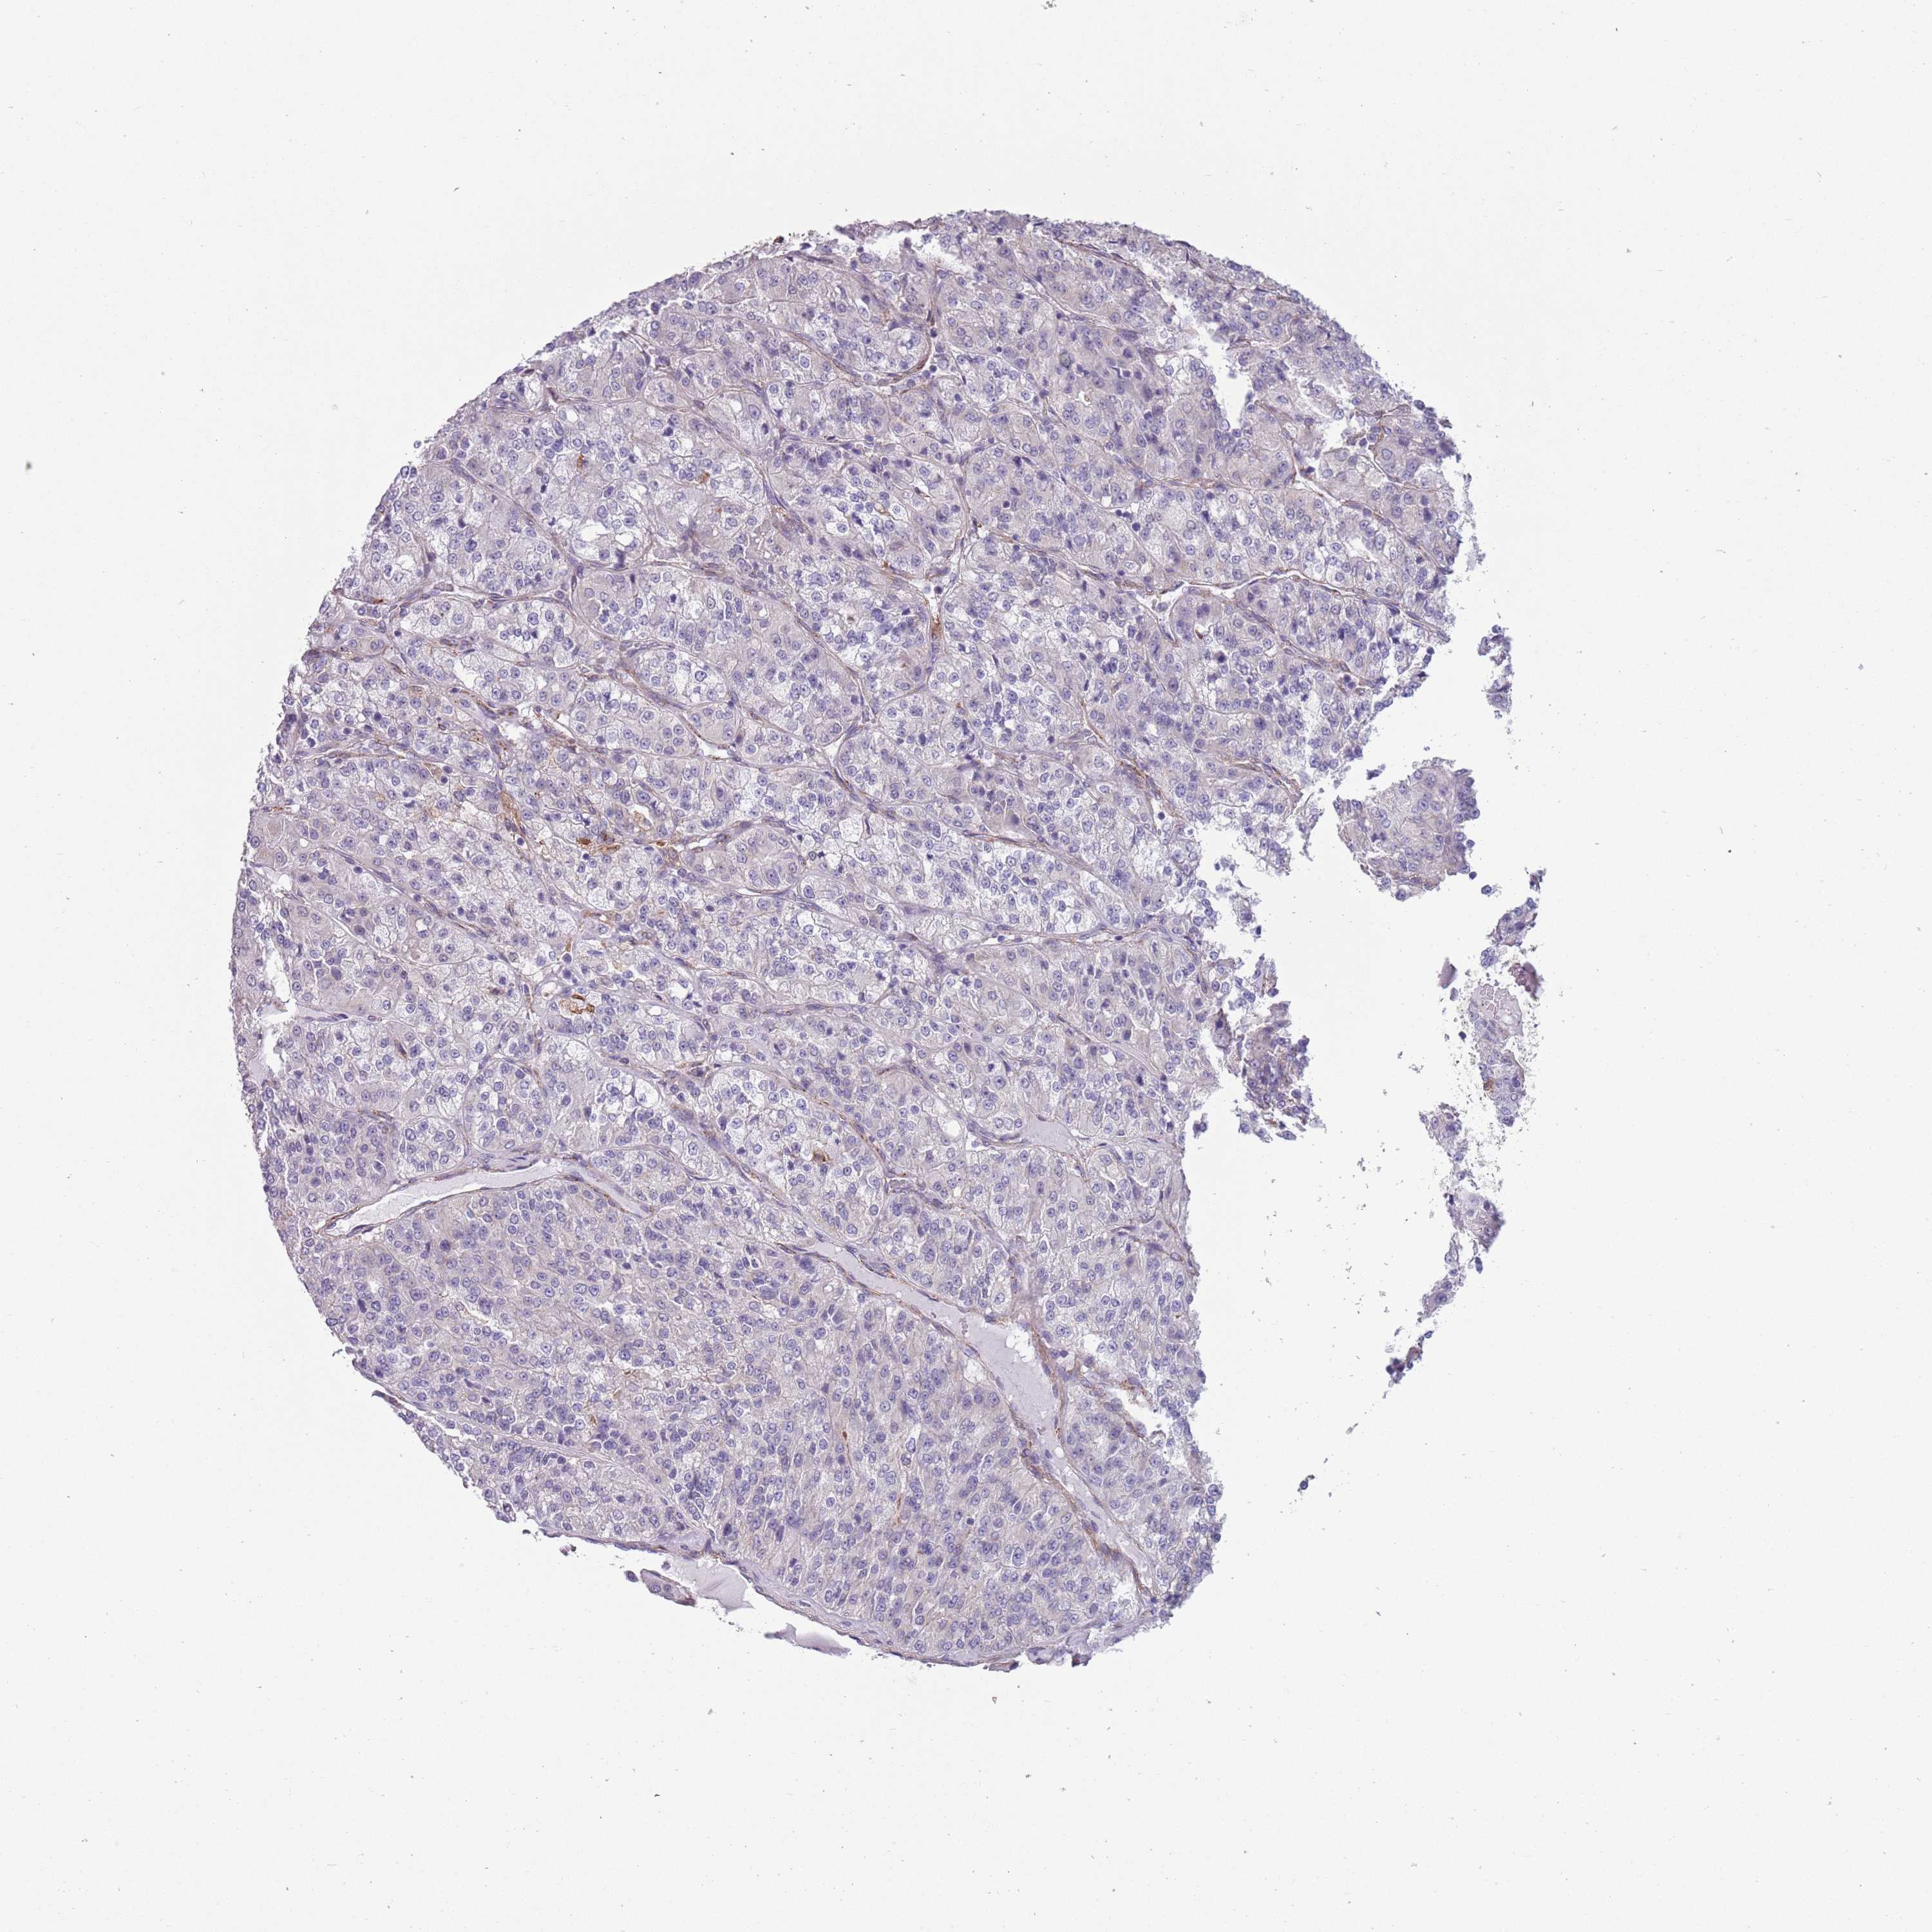

KIDNEY RENAL CLEAR CELL CARCINOMA (VALIDATION) - Interactive survival scatter ploti

The Survival Scatter plot shows the clinical status (i.e. dead or alive) for all individuals in the patient cohort, based on the same data that underlies the corresponding Kaplan-Meier plots. Patients that are alive at last time for follow-up are shown in blue and patients who have died during the study are shown in red.

The x-axis shows the expression levels (FPKM) of the investigated gene in the tumor tissue at the time of diagnosis. The y-axis shows the follow-up time after diagnosis (years). Both axes are complimented with kernel density curves demonstrating the data density over the axes. The top density plot shows the expression levels (FPKM) distribution among dead (red) and alive patients (blue). The right density plot shows the data density of the survived years of dead patients with high and low expression levels respectively, stratified using the cutoff indicated by the vertical dashed line through the Survival Scatter plot. This cutoff is automatically defined based on the FPKM cutoff that minimizes the p-score. The cutoff can be changed by dragging the vertical line or by entering a cutoff value in the square labeled "Current cut-off".

Under the Survival Scatter plot the p-score landscape (black curve; left axis) is shown together with dead median separation (red curve; right axis). Dead median separation is the difference in median mRNA expression between patients who have died with high and low expression, respectively. It is calculated as follows: median FPKM expression of dead patients with high expression - median FPKM expression of dead patients with low expression. This is intended to aid the user in visually exploring custom cutoffs and the associated p-scores and dead median separation.

Individual patient data is displayed and can be filtered by clicking on one or more of the category buttons on the top of the page. Categories describing expression level and patient information include: high, low, alive, dead, female, male and tumor stages. The scale of the x-axis can be toggled between linear and log-scale by clicking on the "x log" button. Mouse-over function shows TCGA ID, patient information and mRNA expression (FPKM) for each patient.

& Survival analysisi

Kaplan-Meier plots summarize results from analysis of correlation between mRNA expression level and patient survival. Patients were divided based on level of expression into one of the two groups "low" (under cut off) or "high" (over cut off). X-axis shows time for survival (years) and y-axis shows the probability of survival, where 1.0 corresponds to 100 percent.

CREBZF is not prognostic in Kidney Renal Clear Cell Carcinoma (validation)

: 12.87

Average pTPM 15.4

Number of samples 100